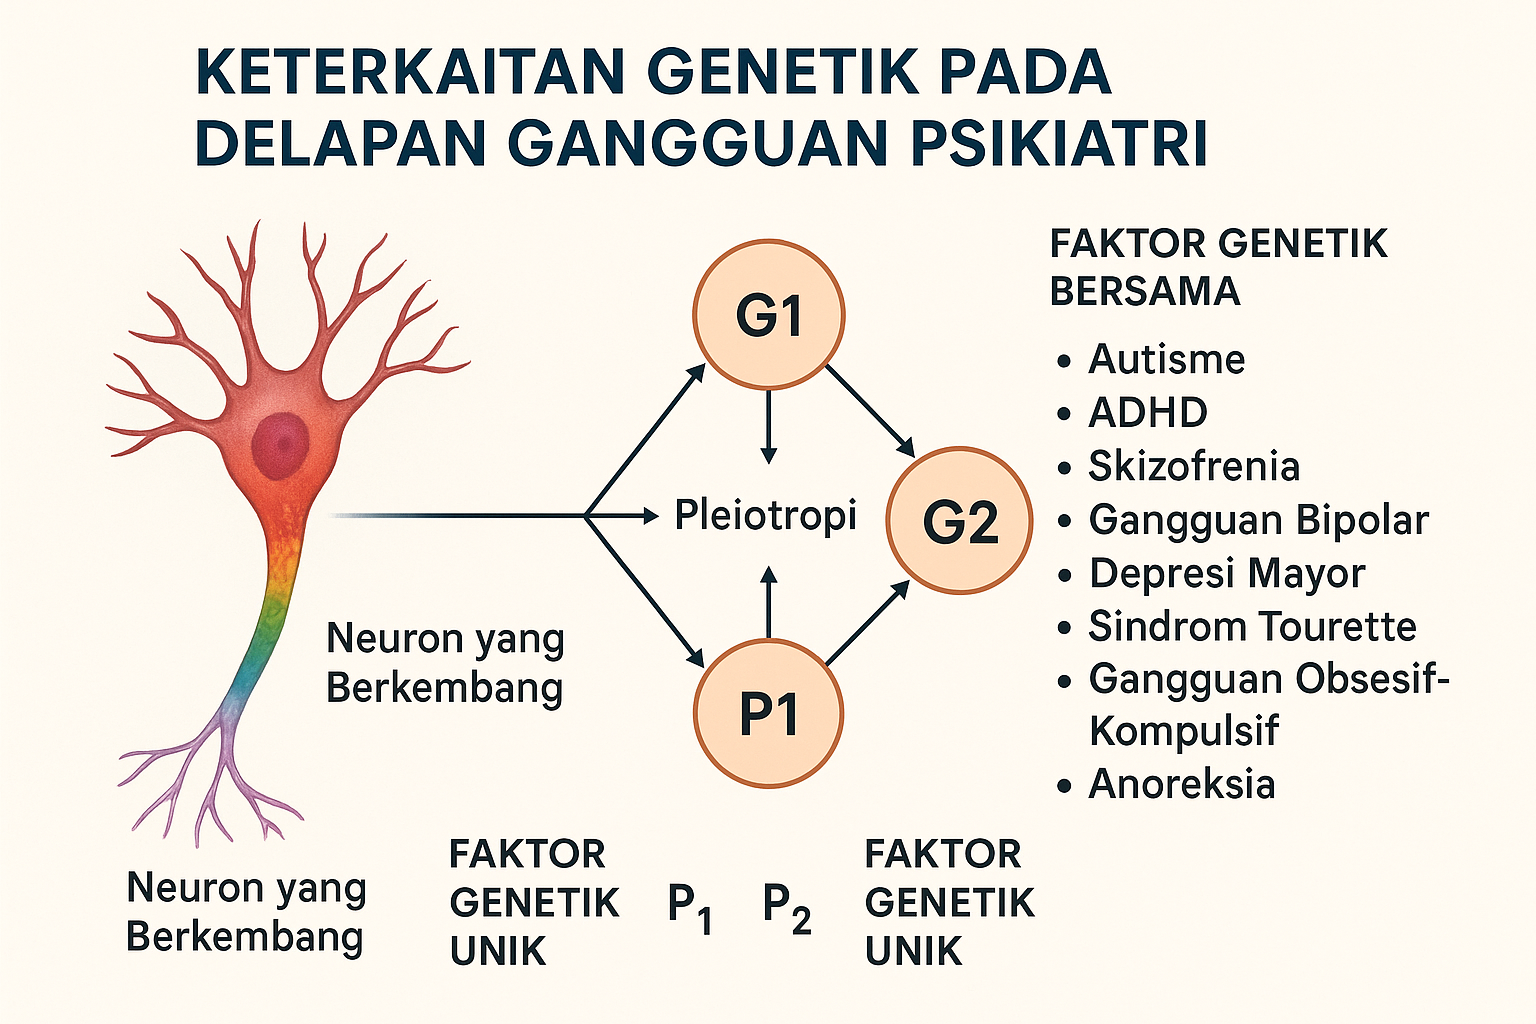

Kecambah Brokoli Bisa Membantu Mengobati Skizofrenia

Skizofrenia ditandai dengan berbagai gejala seperti halusinasi, delusi dan pemikiran, perasaan, perilaku, persepsi dan berbicara yang kacau. Obat yang digunakan untuk mengobati skizofrenia saat ini tidak selalu berhasil pada semua orang. Selain itu dapat menyebabkan berbagai efek samping yang tidak diinginkan, seperti peningkatkan risiko kardiovaskular, gerakan tak terkendali, kegelisahan, kekakuan, dan “tremor.” Dalam serangkaian penelitian menggunakan hewan dan manusia, para peneliti...